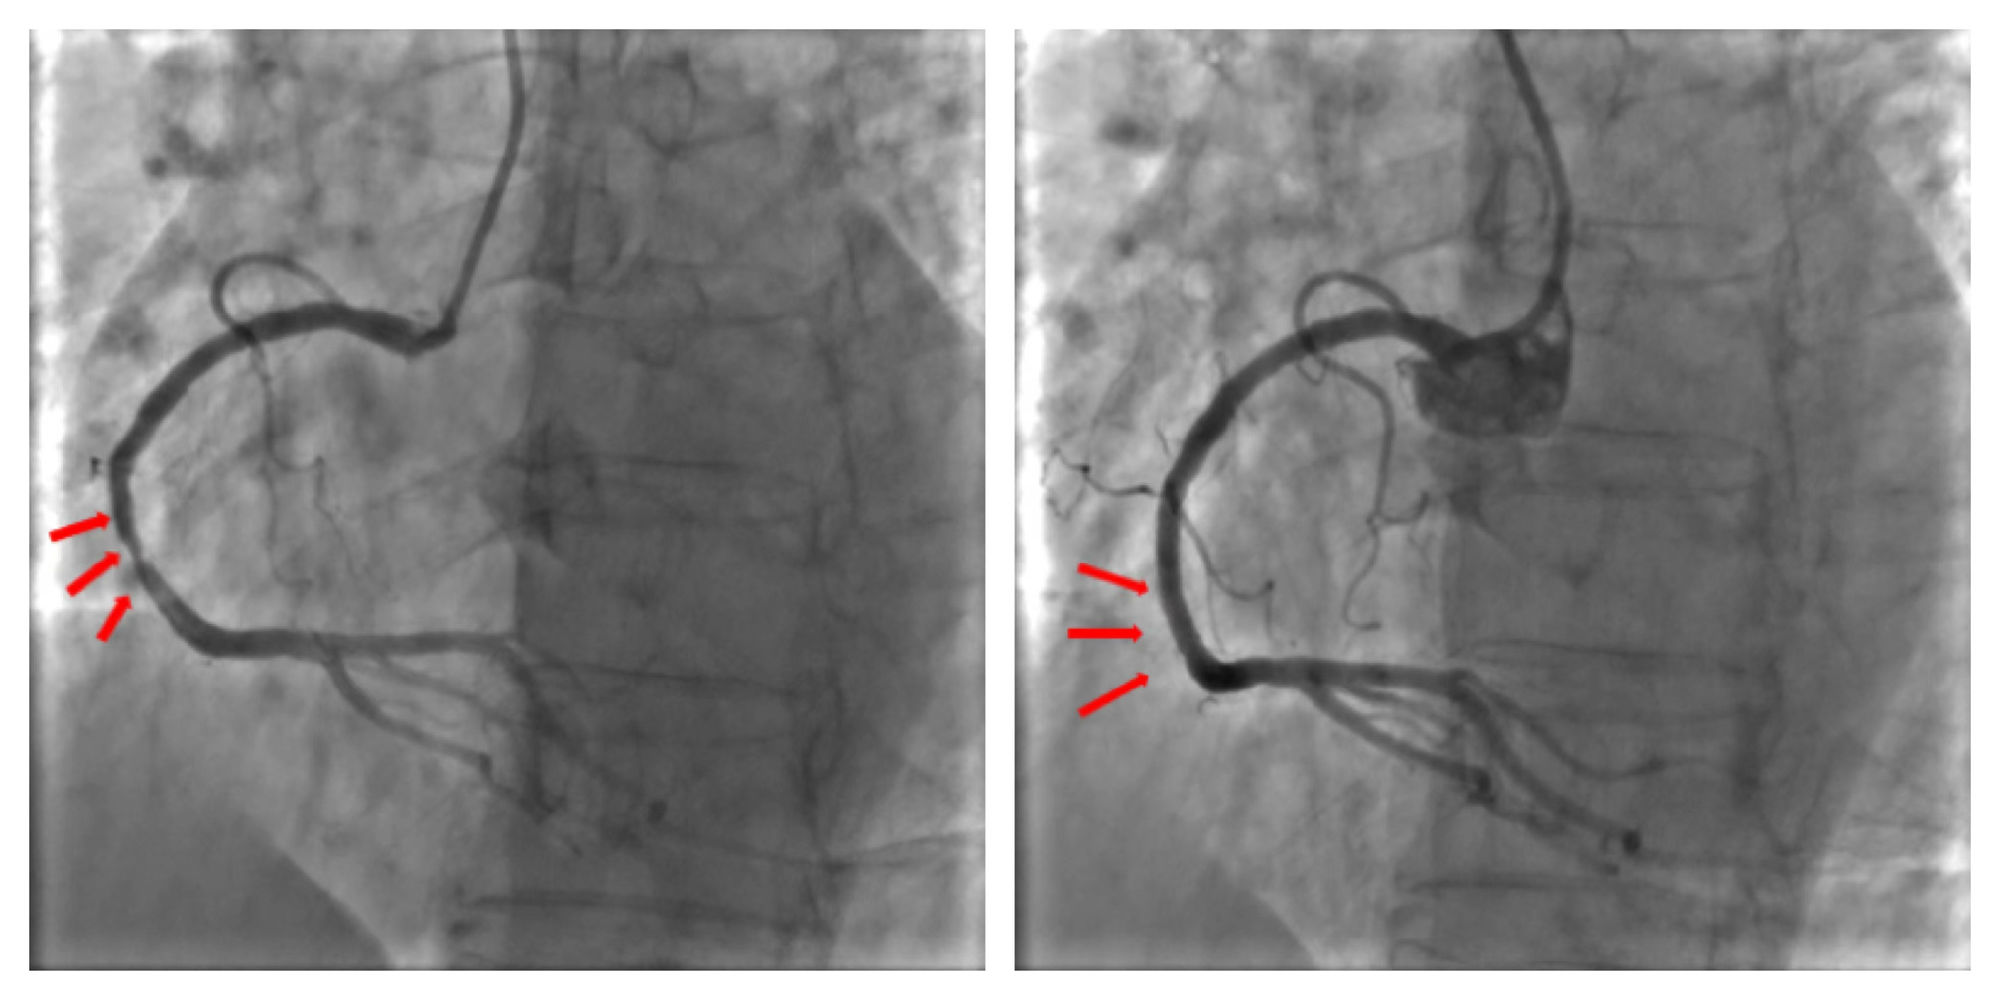

IBS®冠脉支架中国确证性临床研究的首例受试者入组由俞梦越教授率其团队顺利开展。术中冠脉造影提示:单支血管病变,右冠中段狭窄80%,在光学相干断层成像(OCT)指导下,成功完成靶血管的血运重建,右冠中段植入1枚支架,术中无任何并发症发生,达到预期治疗效果,患者术后生命体征平稳。